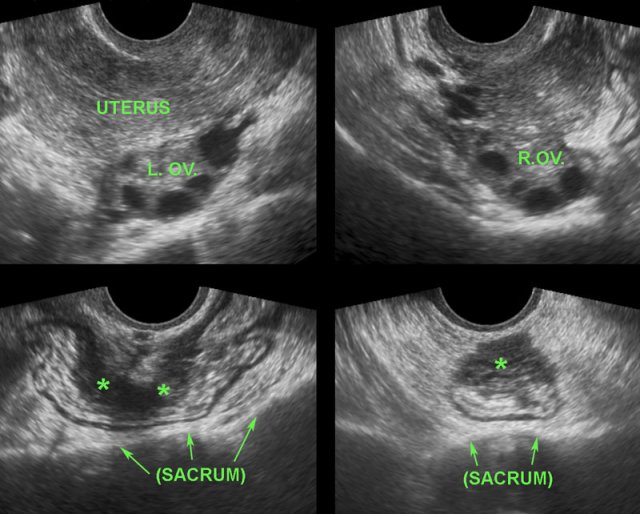

DIE of the rectum

The images are of a patient with DIE and a normal aspect of uterus and ovaries.

DIE has typical, almost pathognomonic TVUS features.

Although obviously a gynaecological condition, it is not infrequently overlooked by gynaecologists during TVUS.

The reason is that the majority of patients with DIE (*), lack the typical endometriotic cysts and have, as in the patient here, a normal uterus and ovaries (L. OV. and R. OV.). Furthermore, the TVUS diagnosis of DIE requires thorough knowledge of the US image of normal and pathological bowel and bladder, which knowledge may be absent in gynaecologists.

DIE implants on the outer surface of the colon in four different patients.

DIE implants (*) in Douglas pouch, are asymmetrically localized, solid, hypoechoic, poorly vascularized masses, which are continuous with the outer hypoechoic muscularis layer of the colon.

The overlying hyperechoic submucosa,  and also the colonic mucosa are generally intact. This explains also why blood in the stool is quite rare in DIE.

The outer contour of these hypoechoic masses is mostly firmly adherent to uterus and/or cervix. Often there is spiculation or “tethering” visible on the outer margins.

Adherence to the uterus and cervix can be demonstrated by gently pushing with the probe to-and-fro.

Whereas the normal sigmoid and rectum can easily be pushed away from the uterus with the probe (“sliding phenomenon”), the adhesions (arrow) belonging to DIE (*) block the entrance of the probe into the posterior fornix.